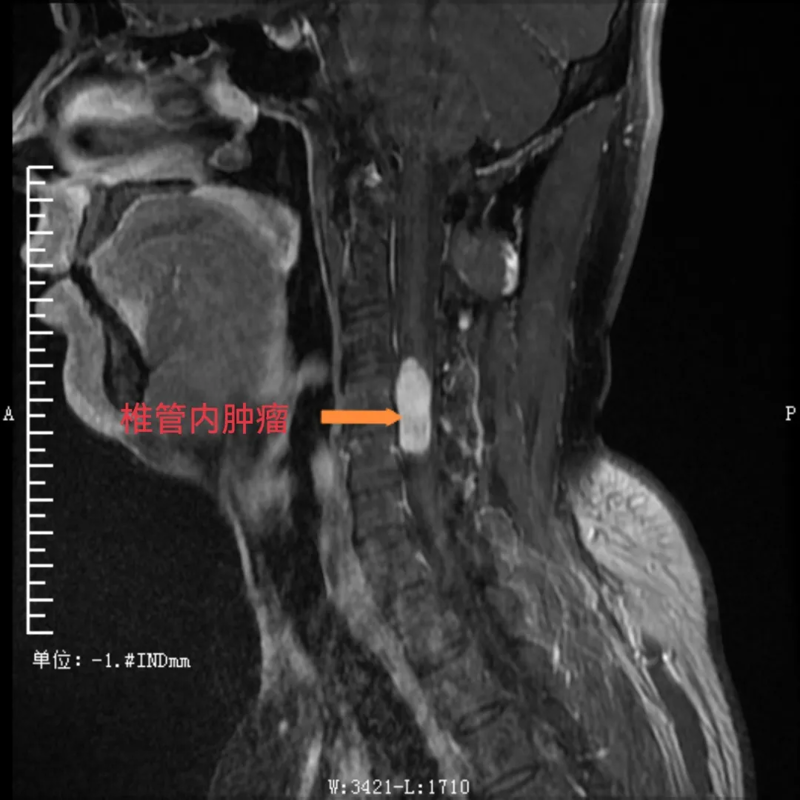

患者潘某(化名),是一位38岁的男性,一直被“左上肢感觉异常、乏力”的症状困扰8个多月。起初,他在贵州荔波县当地医院进行诊治,后根据患者意愿,转到河池市三医院神经外科接受进一步诊疗,到院后,经检查,明确了他的病因:原来是颈椎4-5节段椎管内长了肿瘤。这一肿瘤的存在严重影响了他的神经功能,导致了上肢的不适症状。对于患者来说,这无疑是一个沉重的打击。

术前,可见椎管内肿瘤